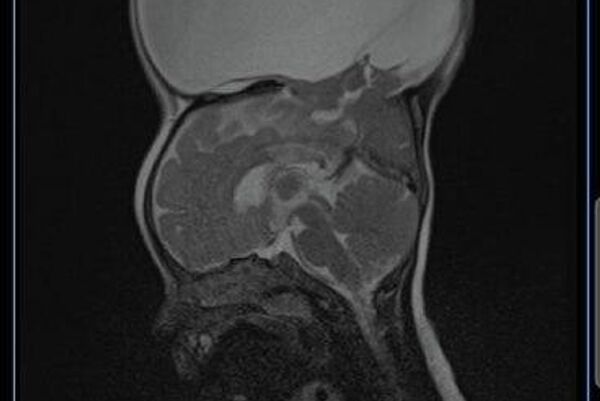

ይህ በስድስት ወር ጨቅላ ላይ የታየው ግዙፍ የጭንቅላት ላይ እብጠት "ኤንሰፋሎሲል" የሚባል የነርቭ ቱቦ እክል ሲሆን፣ ፅንስ በማህፀን ውስጥ እያለ የራስ ቅል አጥንት በትክክል ሳይዘጋ ሲቀር የሚከሰት ነው።

የሕክምና ቡድኑ ከሁለት ሰዓት ተኩል በላይ በቆየ ቀዶ ሕክምንና፣ የደም ሥሮቹን ሳይነኩ እብጠቱን የመለየት አስቸጋሪ ፍልሚያ በማካሄድ በስኬት ማጠናቀቃቸው ተገልጿል፡፡ ሕጻኗ በአሁኑ ወቅት በጥሩ ጤንነት ላይ እንደምትገኝ የአገር ውስጥ ሚዲያ የሆስፒታሉን ባለሙያዎች ጠቅሶ ዘግቧል።

ኤንሰፋሎሲል፣ እናቶች በእርግዝና ወቅት ወይም ከመፀነሳቸው በፊት ፎሊክ አሲድ በመውሰድ ሊከላከሉት የሚችሉት የጤና እክል መሆኑ ተመላክቷል።